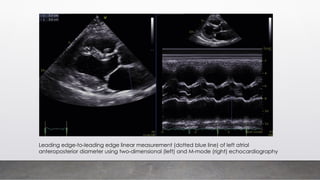

Leading edge-to-leading edge linear measurement (dotted blue line) of left atrial

anteroposterior diameter using two-dimensional (left) and M-mode (right) echocardiography